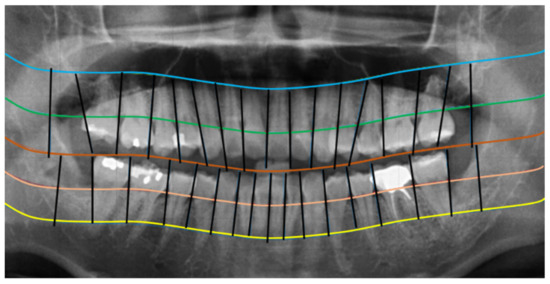

2.2.1. Curve of the Mouth

2.2.2. Curve Adjustment

2.2.3. Positioning Numbers